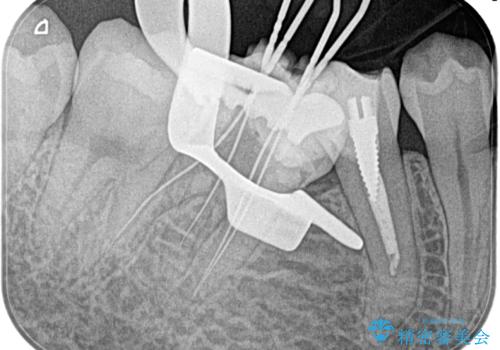

【湾曲根管】奥歯がズキズキ痛い

- 奥歯が1週間前からズキズキ痛いことを主訴に来院されました。

診査の結果、不可逆性歯髄炎と診断し抜髄処置を行っております。

【使用ファイル】NEX-MS

【充填法】Hydraulic Condensation